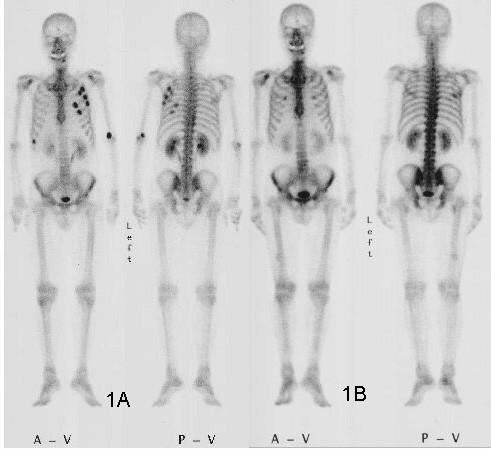

Another kind of point detector for X-rays and other kinds of radiation is the scintillation counter. These use a crystal, often cesium iodide or sodium iodide doped with thallium, that releases a few visible light photons when it absorbs ionizing radiation. The faint pulse of light is greatly amplified by one or more photomultiplier tubes, creating a pulse of current proportional to the amount of radiation. Nuclear medicine studies use a device called a gamma camera, which has a hexagonal array of PM tubes positioned behind a single large crystal. A patient is injected with a radioisotope such as the gamma-emitting technetium-99, which accumulates mainly in the bones. Gamma rays emitted are collected by the gamma camera, which derives positional information from the differing times of arrival and relative intensity of the light pulse at the PM tubes, slowly building a ghostly skeletal map of the patient by measuring where the 99Tc accumulated.